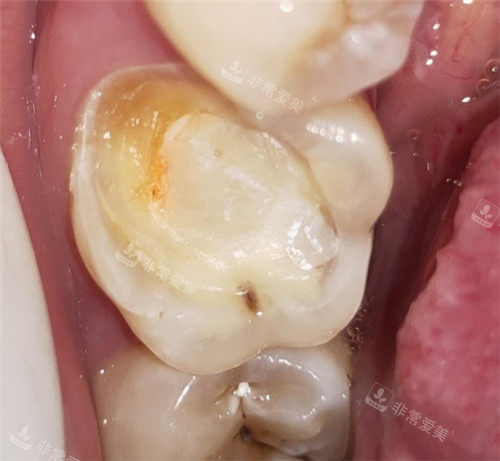

牙齿龋坏图片模型示意图

牙齿龋坏剖面图

牙齿龋坏模型

牙齿龋坏

牙齿龋坏清理图

修复龋坏的牙齿